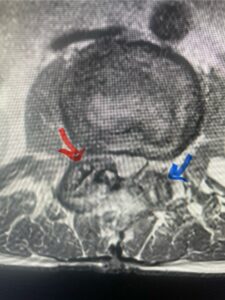

In this next case, this patient is a 47 year-old female who presents with intractable low back pain with severe pain, numbness, and weakness in the right lower extremity that had gotten progressively worse over a year. The patient had failed conservative management including physical therapy and epidurals. She was noted to have ⅘ weakness of plantar flexion. MRI demonstrated a large right L5-S1 disc herniation with severe compression of the descending right S1 nerve root (Fig 3). It was decided to perform a right L5-S1 hemilaminectomy for removal of the disc fragment and decompress the S1 nerve root. When you expose the disc, one must be certain to release any anterior adhesions to the nerve root in order to prevent a dural tear during retraction of the nerve root. It is also important to make sure during exposure and you finally encounter the dura after removing the ligamentum and fat, to make sure you are looking at the nerve root and not the main trunk of the thecal sac because if you don’t you can avulse or damage the nerve root if you retract the wrong structure.

Fig. 3a: Sagittal and axial T2-weighted lumbar MRI images demonstrating large right L5-S1 disc herniation (red arrows)

Fig 1b: Note the left L2-3 facet joint (blue arrow) is normal in size compared to the right (red arrow)